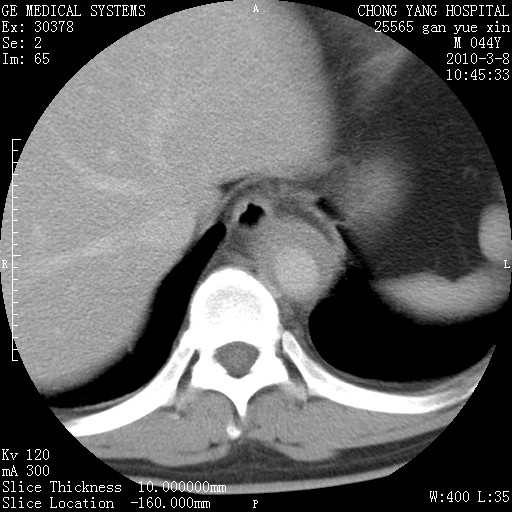

标题: CT24940:主动脉增强,典型病例。 [打印本页]

标题: CT24940:主动脉增强,典型病例。

夹层动脉瘤。

动脉夹层

夹层动脉瘤,典型

主动脉夹层。

动脉夹层的分型:

⒈debakey分型:根据主动脉夹层累及部位,分为三型:ⅰ型:原发破口位于升主动脉或主动脉弓部,夹层累及升主动脉、主动脉弓部、胸主动脉、腹主动脉大部或全部,少数可累及髂动脉。ⅱ型:原发破口位于升主动脉,夹层累及升主动脉,少数可累及部分主动脉弓。ⅲ型:原发破口位于左锁骨下动脉开口远端,根据夹层累及范围又分为ⅲa,ⅲb。ⅲa型:夹层累及胸主动脉。ⅲb型:夹层累及升主动脉、腹主动脉大部或全部。少数可累及髂动脉。

⒉stanford分型:a型:夹层累及升主动脉,无论远端范围如何。b型:夹层累及左锁骨下动脉开口以远的降主动脉。

夹层动脉瘤,少量胸水

夹层动脉瘤;左侧少量胸腔积液。

典型主动脉夹层。